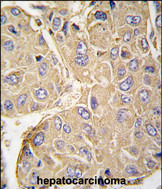

- Experimental details

- Formalin-fixed and paraffin-embedded human hepatocarcinoma tissue reacted with PTPN7 Antibody (S44) (GTX81369), which was peroxidase-conjμgated to the secondary antibody, followed by DAB staining. This data demonstrates the use of this antibody for immunohistochemistry; clinical relevance has not been evaluated.